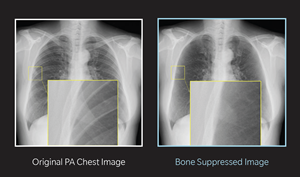

Konica Minolta’s BSI suppresses the ribs and the clavicle from standard chest radiographs to enable clearer visualization of the lung and reveal soft-tissue details that may otherwise remain obscured. By improving the visibility of lung structures – even in dense or complex regions – BSI enhances diagnostic clarity and the radiologist’s confidence in identifying subtle findings such as nodules, interstitial markings, consolidations or early signs of pathology.

Beyond efficiency, BSI has demonstrated tangible clinical benefits. By digitally suppressing bony structures, radiologists can achieve opportunistic visualization of abnormalities that may not be immediately apparent on a routine chest radiograph. In numerous cases, this has enabled the team at Zwanger-Pesiri Radiology to detect subtle findings earlier, supporting timely follow-up and more proactive patient care.